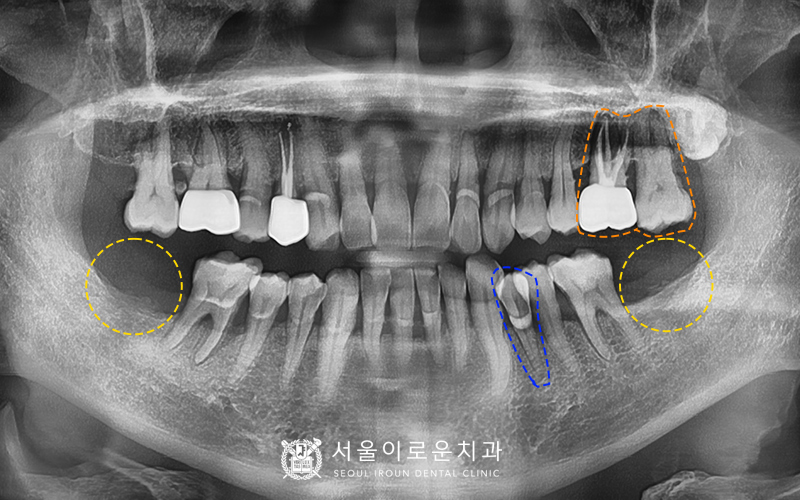

본.원에 처음 오셨던 60대 남성분의 사진입니다.

왼쪽 위에 큰 어금니를 보시면 과거 타원에서 신경치료를 했으나

뿌리 끝에 염증이 생긴 것을 알 수 있었습니다.

바로 옆에 위치한 어금니도 상태가 좋지 않았는데요.

치주염이 많이 진행되어

치아가 심하게 흔들리는 상태였습니다.

또한, 아래 양쪽 큰 어금니가 1개씩 상실된 상태였습니다.

수술에 앞서, CT 촬영을 시행하였습니다.

환.자분의 경우, 아래의 상태로

더욱 꼼꼼한 체크가 필요하였습니다.

1) 60대라는 점

2) 고혈압을 갖고 계신다는 점

3) 잦은 흡연을 하신다는 점